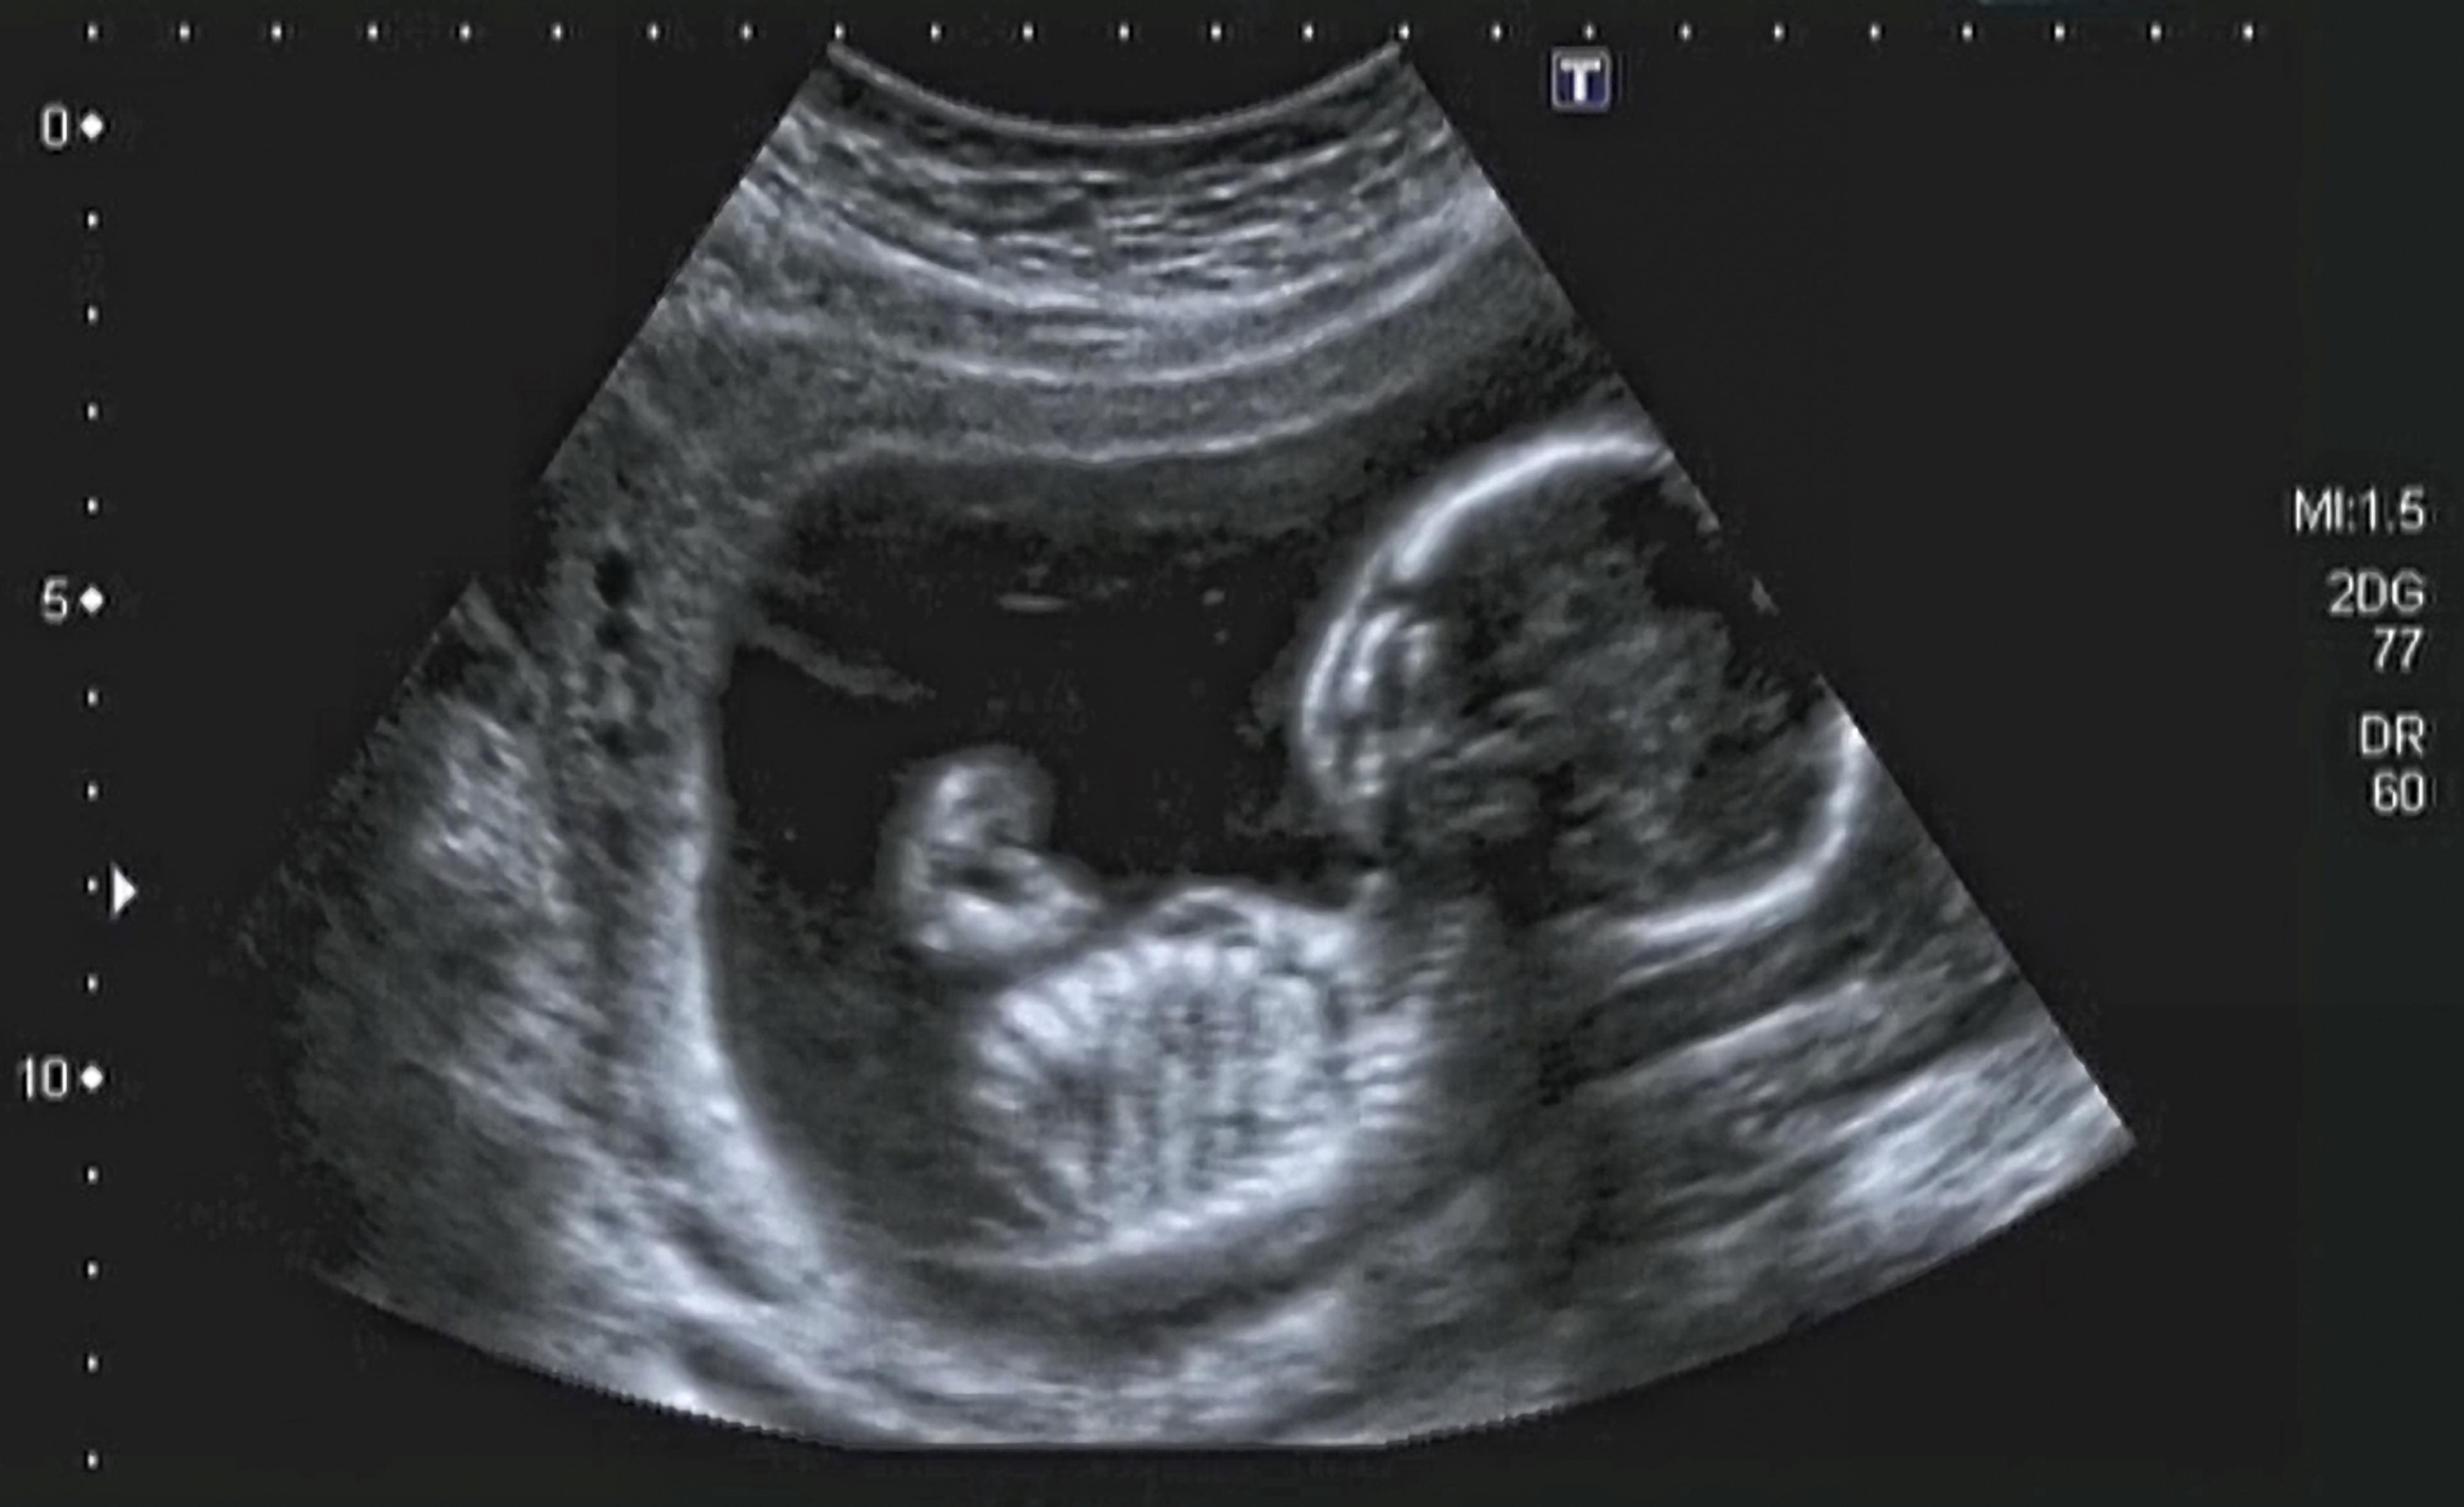

Raskaana oleville tarjotaan sikiöseulontatutkimuksia, joihin osallistuminen on vapaaehtoista. Seulontatutkimukset ovat odottajalle maksuttomia. Riittävän informaation jälkeen raskaana oleva päättää itse, haluaako osallistua tutkimuksiin. Mielipiteen osallistumisesta voi muuttaa missä tahansa seulonnan vaiheessa ilman, että se vaikuttaa raskauden seurantaan tai hoitoon. Sikiöseulontatutkimuksia ovat ultraäänitutkimukset, äidin verinäytteestä määritettävät merkkiaineet sekä näiden yhdistelmät. Poikkeava seulontatulos ei merkitse sikiön sairautta, vaan sikiöpoikkeavuuden kohonnutta riskiä. Normaali seulontatulos ei takaa tervettä lasta.